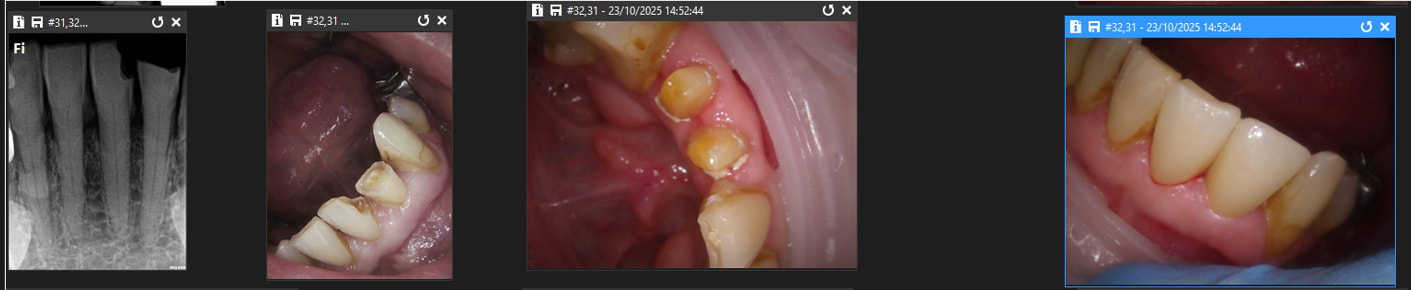

Comparaison des traitements de 2 praticiens différents au même tarif. Même patient 16 26. Pourquoi se faire chier aucun souci sur 26. ,

> Comparaison des traitements de 2 praticiens différents au même tarif. Même

> patient 16 26. Pourquoi se faire chier aucun souci sur 26. ,

Indépendamment du reste, il y a clairement une racine MV non traitée dont on distingue le canal, ce qui est l'anatomie standard d'une 26.

Conclusion, le praticien l'a sciemment ignorée pour aller plus vite.

On peut discuter de la rémunération, des raisons qui ont amené ce praticien à choisir de bâcler le travail, mais il est indiscutable que le praticien ne peut pas avoir ignoré avoir fait n'importe quoi.

J'ai bien précisé que tout n'est pas facile. Cette 26 l'est, je n'ai quasiment aucun doute.